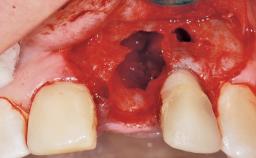

Immediate Flapless Placement of an Implant in a Maxillary Left Central Incisor Site

A 42-year-old female patient was referred to our clinic at the School of Dentistry of the University of São Paulo in November 2004, presenting a deficient restoration in the upper left central incisor. The clinical examination revealed no gingival retraction or any signs of gingival inflammation and, therefore, previous periodontal treatment was not considered. The patient presented a high lip line at full smile and a thin tissue biotype. This combination characterized a high-risk situation from an anatomic point of view, which required careful preoperative planning and cautious surgical execution.

Soft Tissue Anatomy Intact Defective

Bone Volume Horizontally and vertically sufficient Horizontally deficient Deficient vertically or deficient vertically AND horizontally

Soft Tissue Contour and Volume Ideal